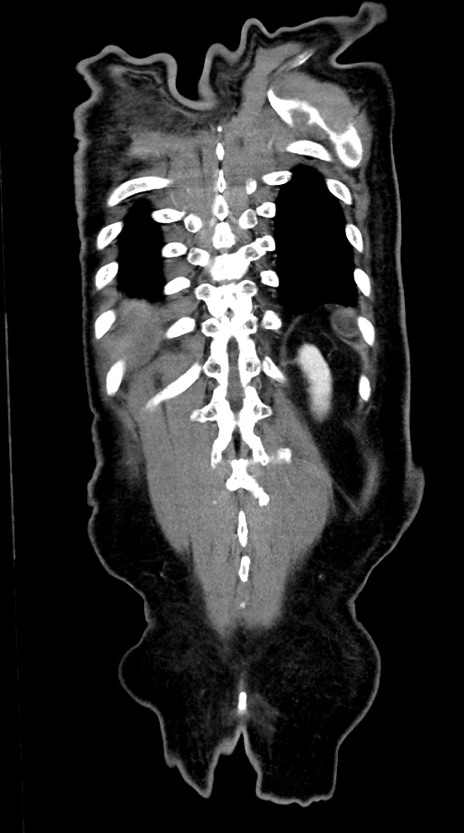

症例28(冠状断像)

【症例】60歳代男性

【主訴】嘔吐

【現病歴】胃癌にて胃全摘後。食思不振が悪化し、夜中に嘔吐することがある。

【既往歴】胃癌、胃全摘、脾摘、胆摘後

【データ】WBC 5900、CRP 10.56